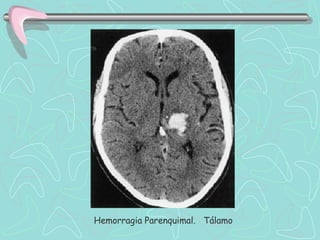

DIAGNÓSTICO

TOMOGRAFÍA COMPUTARIZADA DE ENCÉFALO

•Examen de elección en el Ictus agudo

ICTUS HEMORRÁGICO

•Lesión Hiperdensa que ocupa espacio y desplaza en

diverso grado el parénquima cerebral.

•En HSA puede ser poco hiperdensa, de ubicación

extraparenquimal, e invadir ventrículos cerebrales.

Las Neuroimágenes informan sobre el tipo de lesión, su

tamaño, localización, distribución vascular; la presencia de

complicaciones, y también sobre la necesidad de manejo

quirúrgico.

Hemorragia Parenquimal. Putamen

Hemorragia Parenquimal. Tálamo